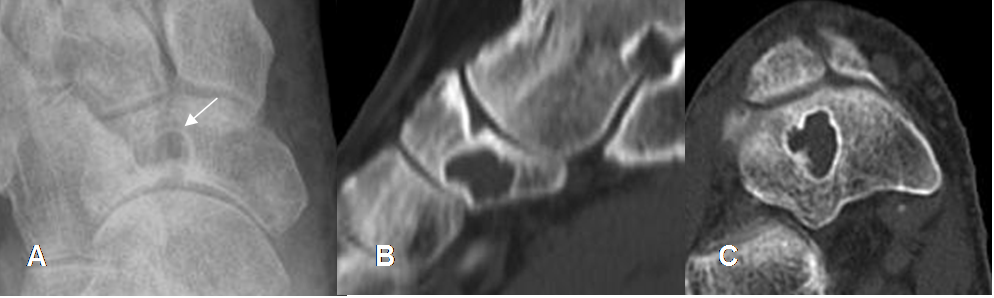

Fig 135. Quiste óseo simple.

A: Rx AP, B: TAC reconstrucción sagital y C: TAC axial. Imagen ovalada y de bordes escleróticos en el escafoides, por quiste simple.